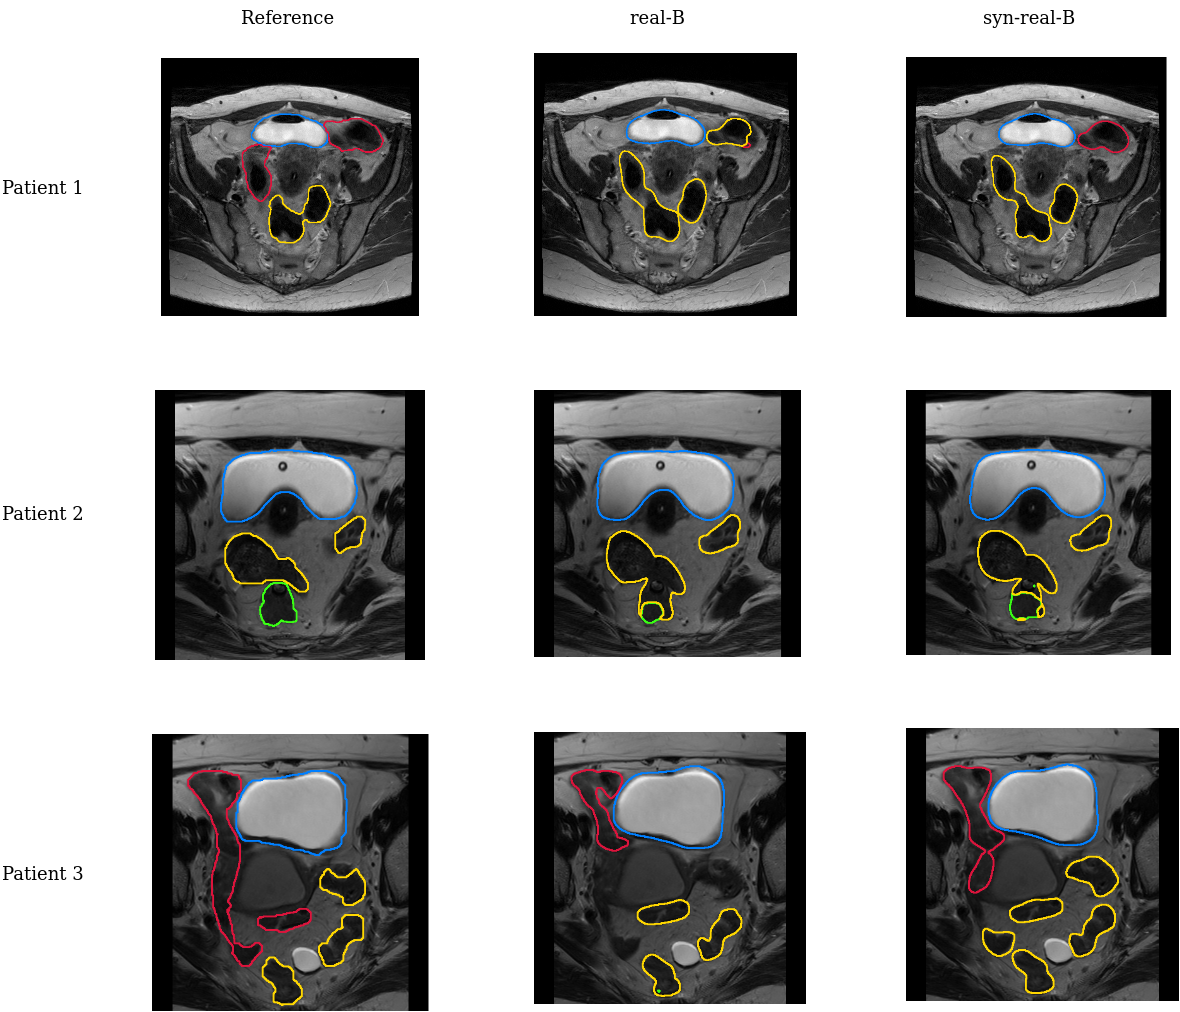

In our experiments, we emulate a distributed setting with sites. As per \sectionrefmet:overview, for each site , GAN- and U-Net-real- are trained and used to generate a synthetic dataset. U-Net-syn-all is trained on the merged datasets and fine-tuned at each site to get U-Net-syn-real-. U-Net-real-all is trained on merged real data as a baseline. All the experiments are performed via five-fold cross-validation (3 folds for training, 1 fold for validation and test each). The mean and the standard deviation of the Dice Score (DS) and the 95th percentile of the Hausdorff Distance (HD95) across the folds are reported. All the evaluations were performed on real data. The results of statistical testing are given in Appendix A. Appendix D contains comparisons with federated learning baselines. The ablations of pretraining with single-site synthetic data and of using the standard StyleGAN2 architecture are reported in Appendices F, G.

\figurereffig:cervix shows that in the experiments with Cervix, DS and HD95 metrics improve in most cases. The performance on site A is approximately the same across the real-A, syn-real-A, real-all settings, showing that adding data from site B is not very helpful even if it is real data. This is likely due to the large number and uniformity of patients in A itself. Nonetheless, the performance in the syn-real-A setting on site B is improved compared to real-A (by 3.3 DS and 4.3 HD95 on average), showing that pretraining on merged synthetic data improves the robustness of the model to data shifts. For site B, the pretrained and fine-tuned model (syn-real-B) outperforms its counterpart trained exclusively on the local data (real-B) when tested on both A (by 6.3 DS and 4.3 HD95 on average) and B (by 2.2 DS and 2.5 HD95 on average). The full results for all datasets are given in Appendix B.

Table B gives per-organ performance for the Cervix dataset. Figure 6 contains slice predictions for qualitative comparison of a real and a syn-real models.